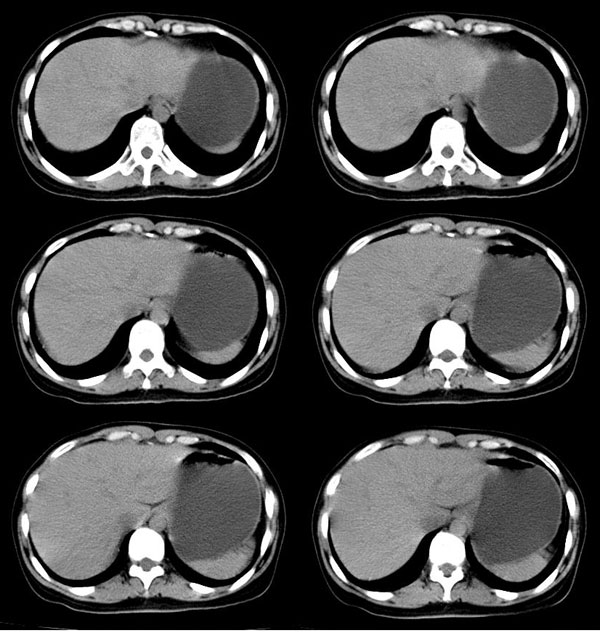

以下是引用guzhongliangddd在2006-11-9 17:55:00的发言:[br]请重点讨论图中箭头所示{脾门部,我首先考虑的是1:血管结构2:胰尾组织??)[br][br][本贴已被 guzhongliangddd 于 2006-11-9 18:01:50 修改过]

以下是引用西北偏北在2006-11-9 20:15:00的发言:[br]箭头所指结构边缘不光整,不支持副脾,考虑胰尾容积层面或血管,做个增强吧.